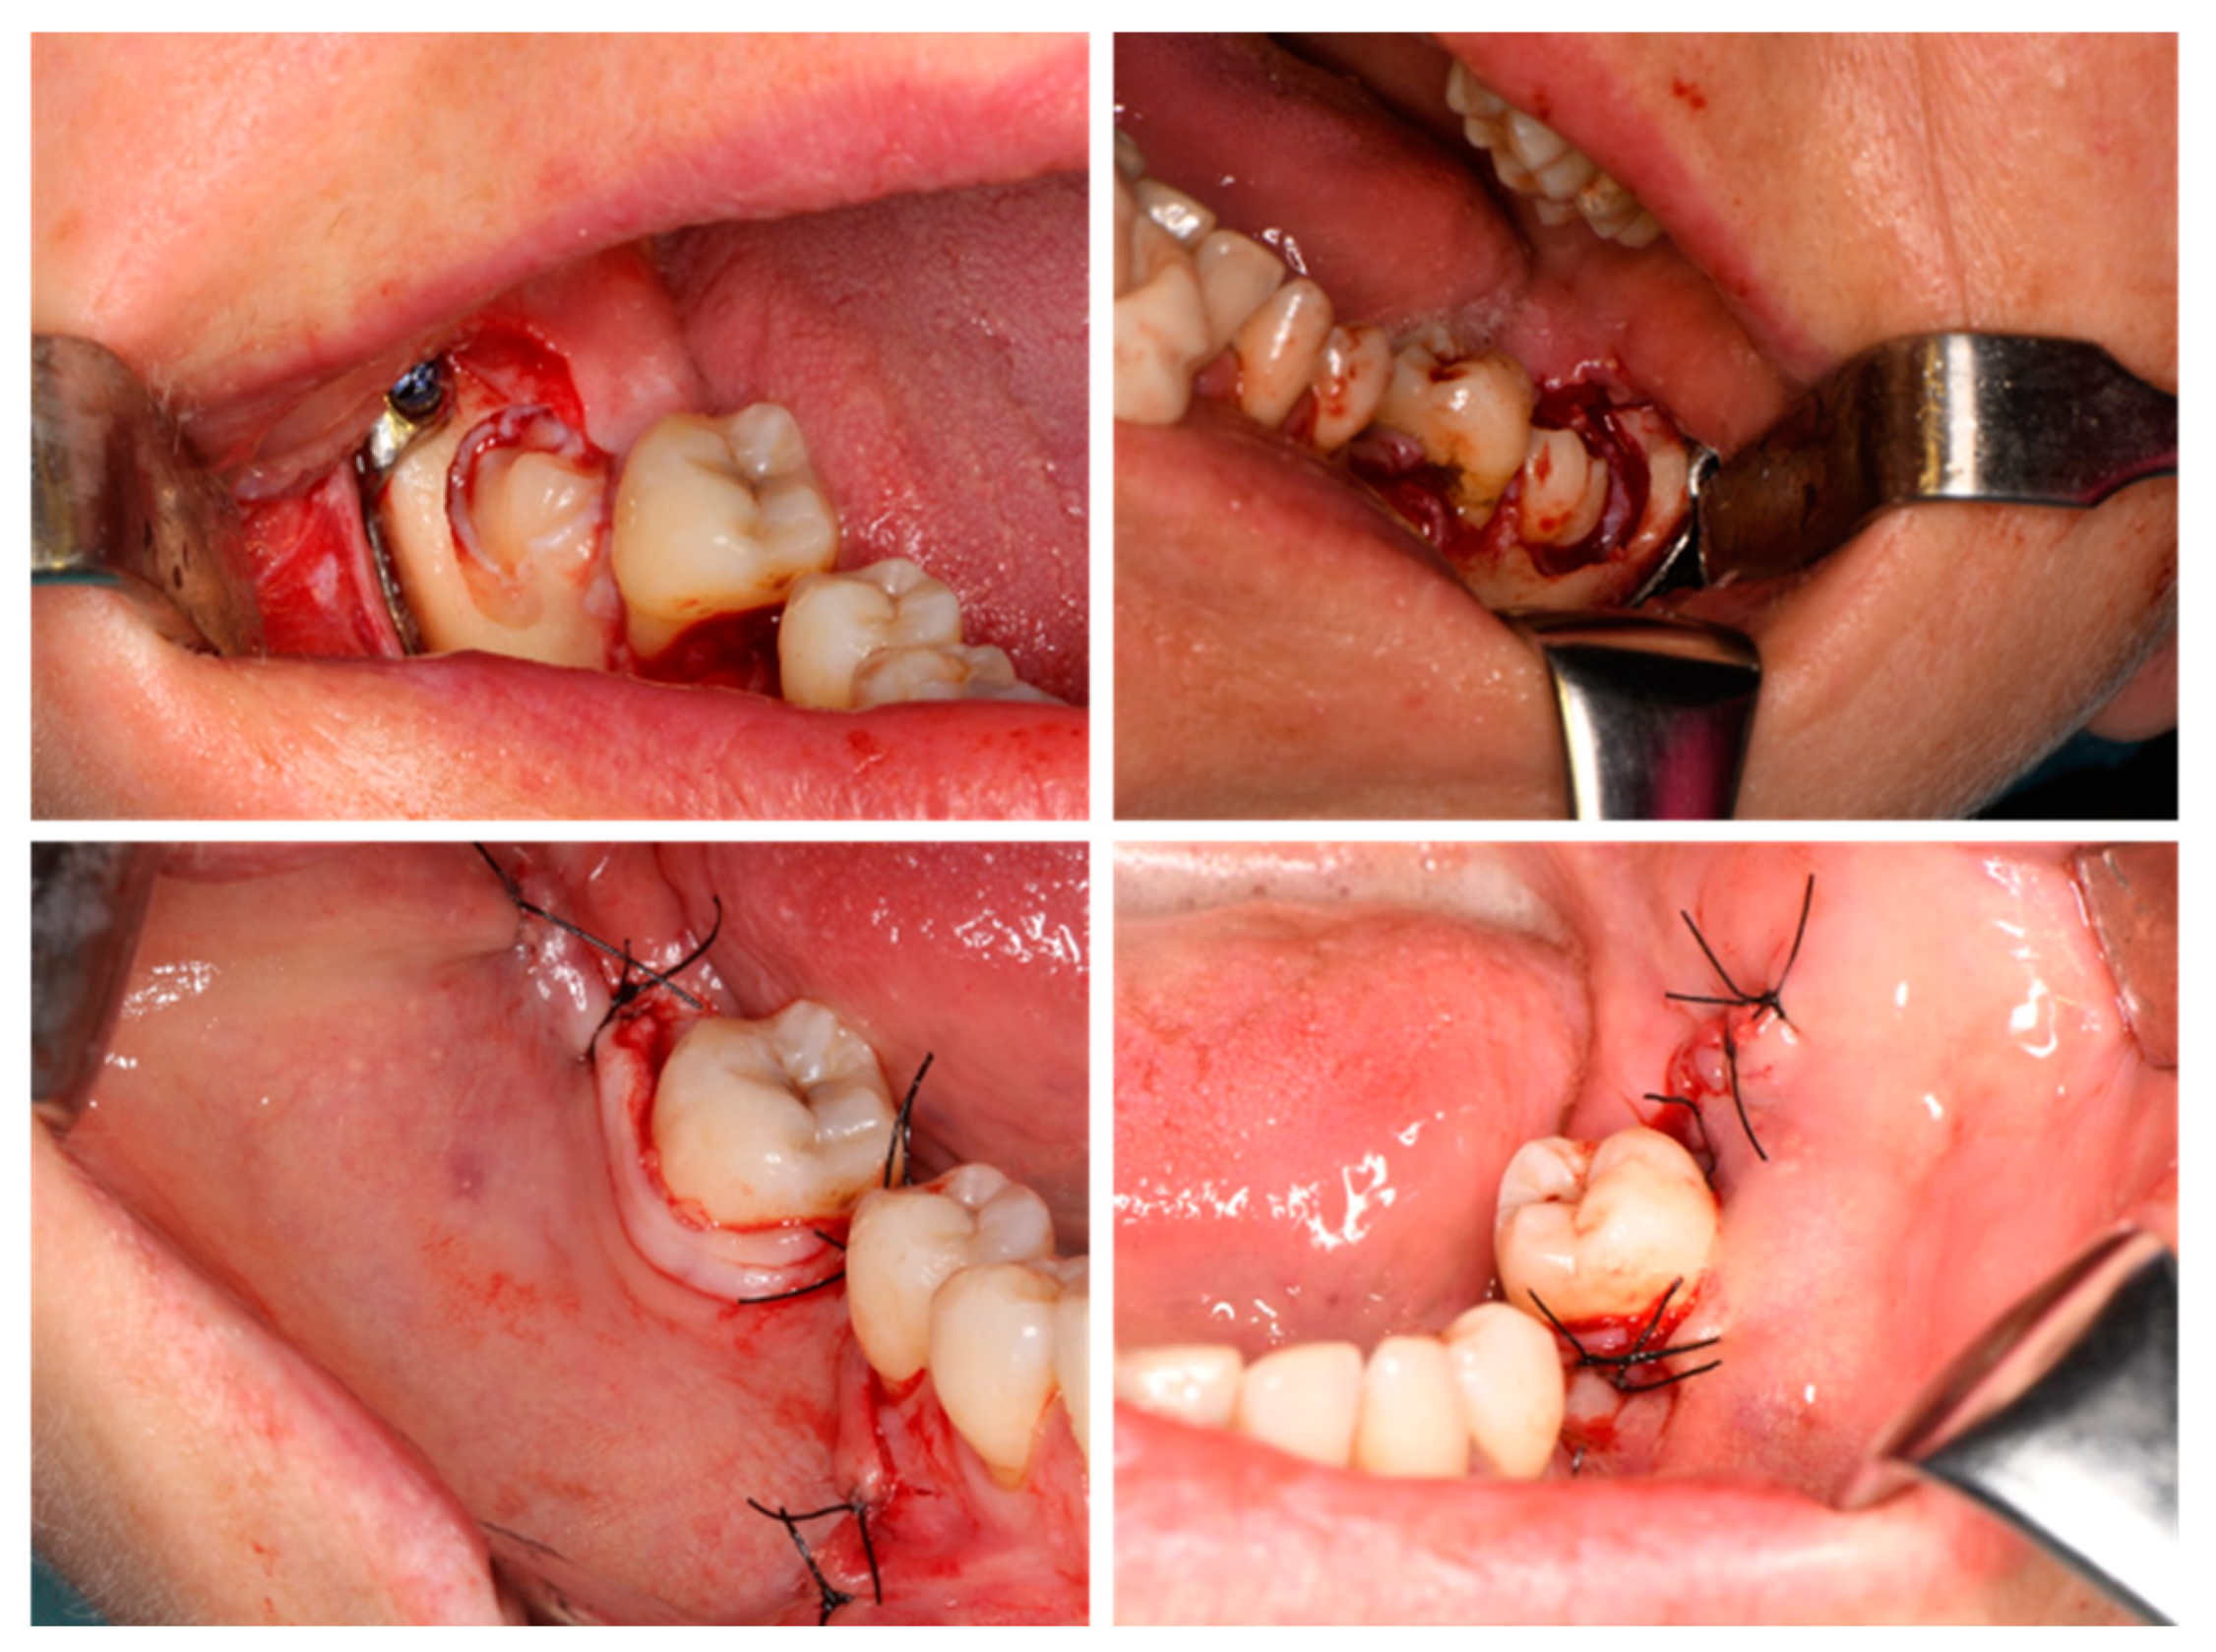

1. Introduction

2. Materials and Methods

2.4. Surgical Procedure